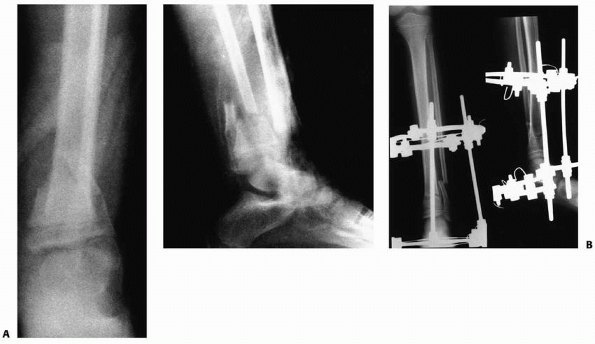

FIGURE 25-27 A. Anteroposterior and lateral radiographs of a grade IIIB open fracture of the distal tibia and fibula. B.

Anteroposterior and lateral radiographs after fracture reduction and stabilization with an Ilizarov circular fixation frame. (From Sharps CH, Cardea JA. Fractures in the shaft of the tibia and fibula. In: MacEwen GD, Kasser J, Heinrich SD, eds. Pediatric Fractures: A Practical Approach to Assessment and Treatment. Baltimore: Williams & Wilkins, 1993:325, with permission.) |